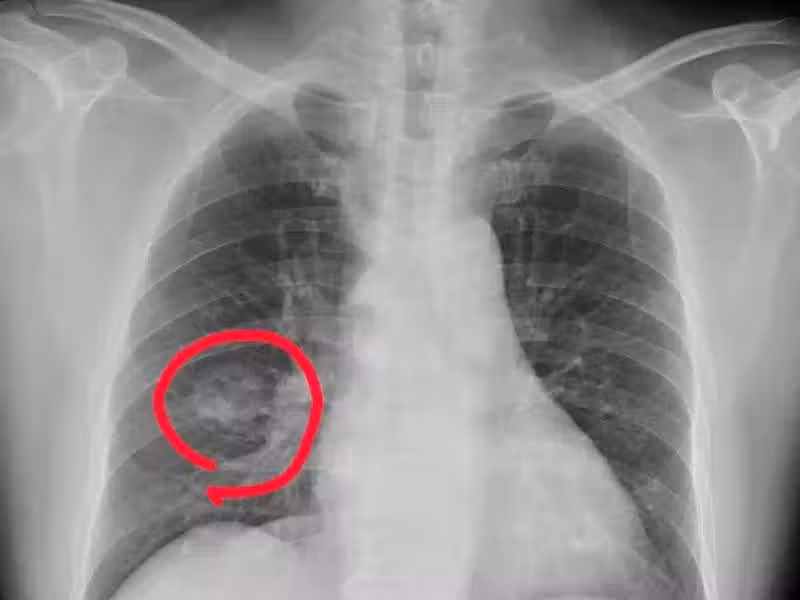

手腳出現 4 種異常,可能是得肺癌了,千萬不要大意

肺癌來臨並非無聲無息,提醒:手腳出現 4 種異常,可能是肺癌到來,不要大意!